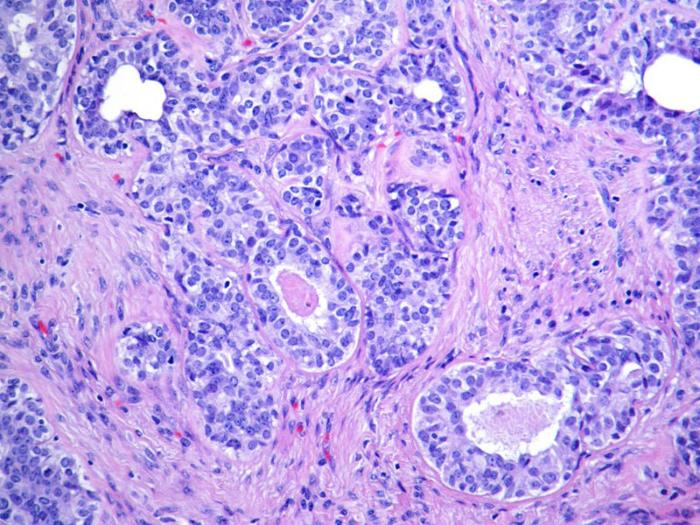

Гистологические характеристики данных опухолей аналогичны таковым у подобных образований в слюнных железах. Разные микроскопические варианты, обнаруженные в аденоидно-кистозной карценоме слюнных желез, могут также проявляться в грудных тканях.

Опухоль состоит из двух типов клеток: люминальных и миоэпителиально-базальных, которые могут располагаться в одном или нескольких архитектурных конфигурациях: трубчато-трабекулярной, крибриформной и солидно-базалоидной.

Есть два типа структур, выстланных этими клетками:

- Люминальные клетки имеют округлые ядра и эозинофильную цитоплазму. Они окружают истинный просвет железы. Реакция с периодической кислотой показывает кислотно-шифф-положительный нейтральный муцин. По иммуногистохимическим характеристикам клетки люминального типа положительны к CK7, CK8/18, антигену эпителиальной мембраны и CD117 (c-Kit).

- Миоэпителиально-базальные клетки обладают центральными овальными ядрами и ограниченной цитоплазмой, формируя псевдолюмин, возникающий в результате инвагинации стромы. Эти клетки имеют иммунореактивность по отношению к базальным цитокератинам (CK5, CK5/6, CK14, CK17), миоэпителиальным маркерам (p63, актин, калпонин, белок S-100), виментина и рецептору эпидермального фактора роста (EGFR).

Гистопатологическое изображение аденоидно-кистозной карциномы, инфильтрирующей нерв (в центре), окраска HE